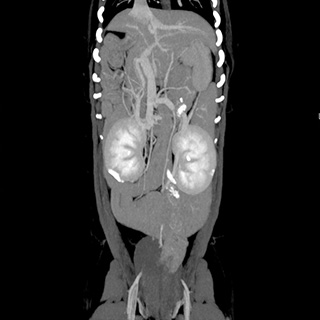

CT画像診断

CT検査により、通常の画像検査では検出しにくい病気の早期発見・診断につながる可能性が高まります。

CT画像の検査・読影のみも受け付けております。当院では画像診断アドバイザーとして柿崎竹彦先生(北里大学獣医学部獣医学科 獣医放射線学研究室講師)からアドバイスをいただいております。